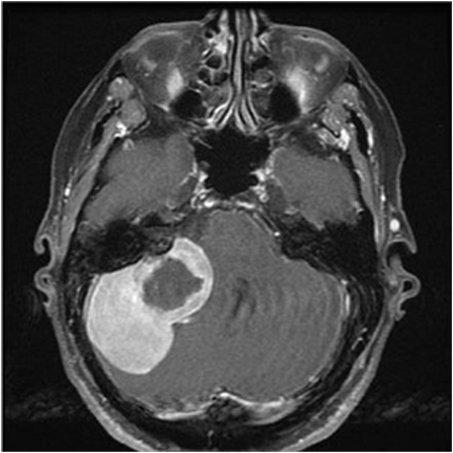

(d) BTMRI dataset

[Uncaptioned image]

Generalization from Base-to-Novel Classes

In our evaluation, we compared the proposed method against several state-of-the-art techniques, including zero-shot CLIP, and prompt learning methods like CoOp, CoCoOp, and MaPLe, thus establishing a robust benchmark for performance assessment. As depicted in Table 7(h), our method outperforms all others in all the medical image recognition datasets. For the base categories, our method demonstrates a remarkable 1.66%percent\% performance improvement. Additionally, when it comes to the novel categories, our method achieves an even more impressive 4.35%percent\% performance improvement. In terms of the harmonic mean, our method elevates the performance from the second-best at 49.45%percent\% to an outstanding 53.08%percent\%. Specifically, our approach excels in the BTMRI dataset, achieving over 3%percent\% performance improvement across all categories. Notably, it achieves a remarkable 5.53%percent\% performance improvement specifically for the novel categories. While our method may not achieve the top performance in terms of novel categories in the CHMNIST dataset, it does obtain the best performance among all prompt-learning methods. Moreover, our method continues to dominate when considering the overall performance evaluation metric, HM. Similar encouraging results are observed in the CCBTM dataset. For the base categories, our method obtains the best performance compared to all prompt-learning methods. Furthermore, the harmonic mean shows a 1.52%percent\% performance gain, further highlighting the strength and effectiveness of our proposed approach.